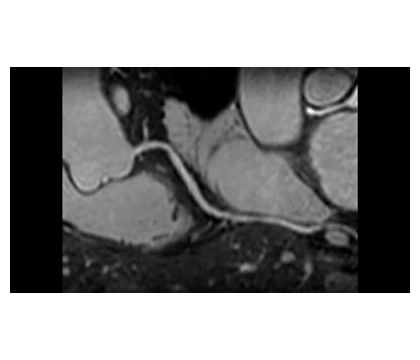

Приложение Coronary Acquisition обеспечивает неинвазивную визуализацию коронарных артерий с высоким уровнем контрастности миокарда и сосудов, позволяя использовать 3D-последовательности в сочетании с навигаторами дыхания MotionTrak для коррекции движения в режиме реального времени и подготовки T2.